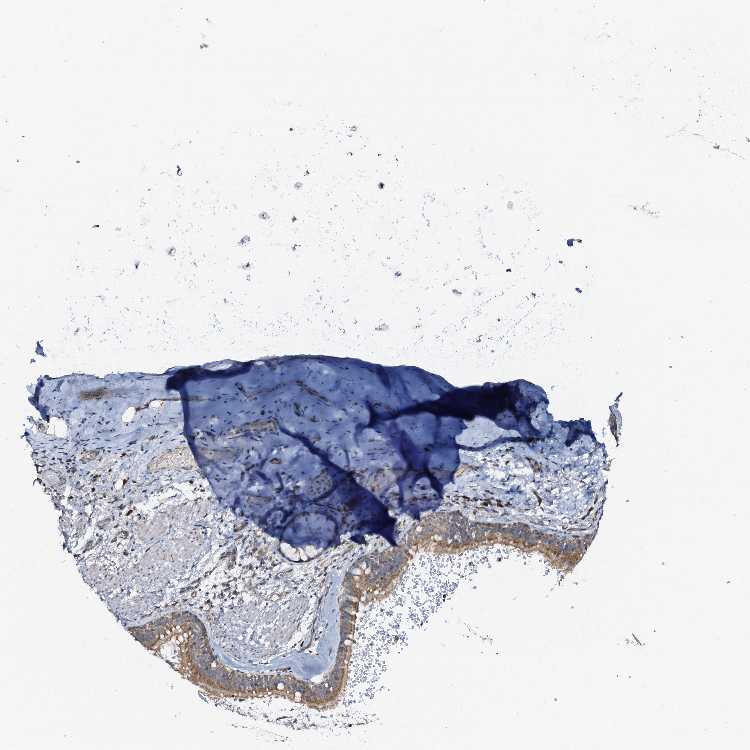

TISSUE PRIMARY DATA SOFT TISSUE Show tissue menu

SOFT TISSUE - Expression summary

SOFT TISSUE 1 - Antibody stainingi

Antibody staining in the annotated cell types in the current human tissue is reported as not detected, low, medium, or high, based on conventional immunohistochemistry profiling in selected tissues. This score is based on the combination of the staining intensity and fraction of stained cells.

Each image is clickable and will lead to virtual microscopy that enables deeper exploration of all samples and also displays staining intensity scores, fraction scores and subcellular localization as well as patient and tissue information for each sample.

Antibody HPA039535Antibody HPA058867

Chondrocytes Not detectedMedium

Fibroblasts LowMedium

Peripheral nerve Medium-